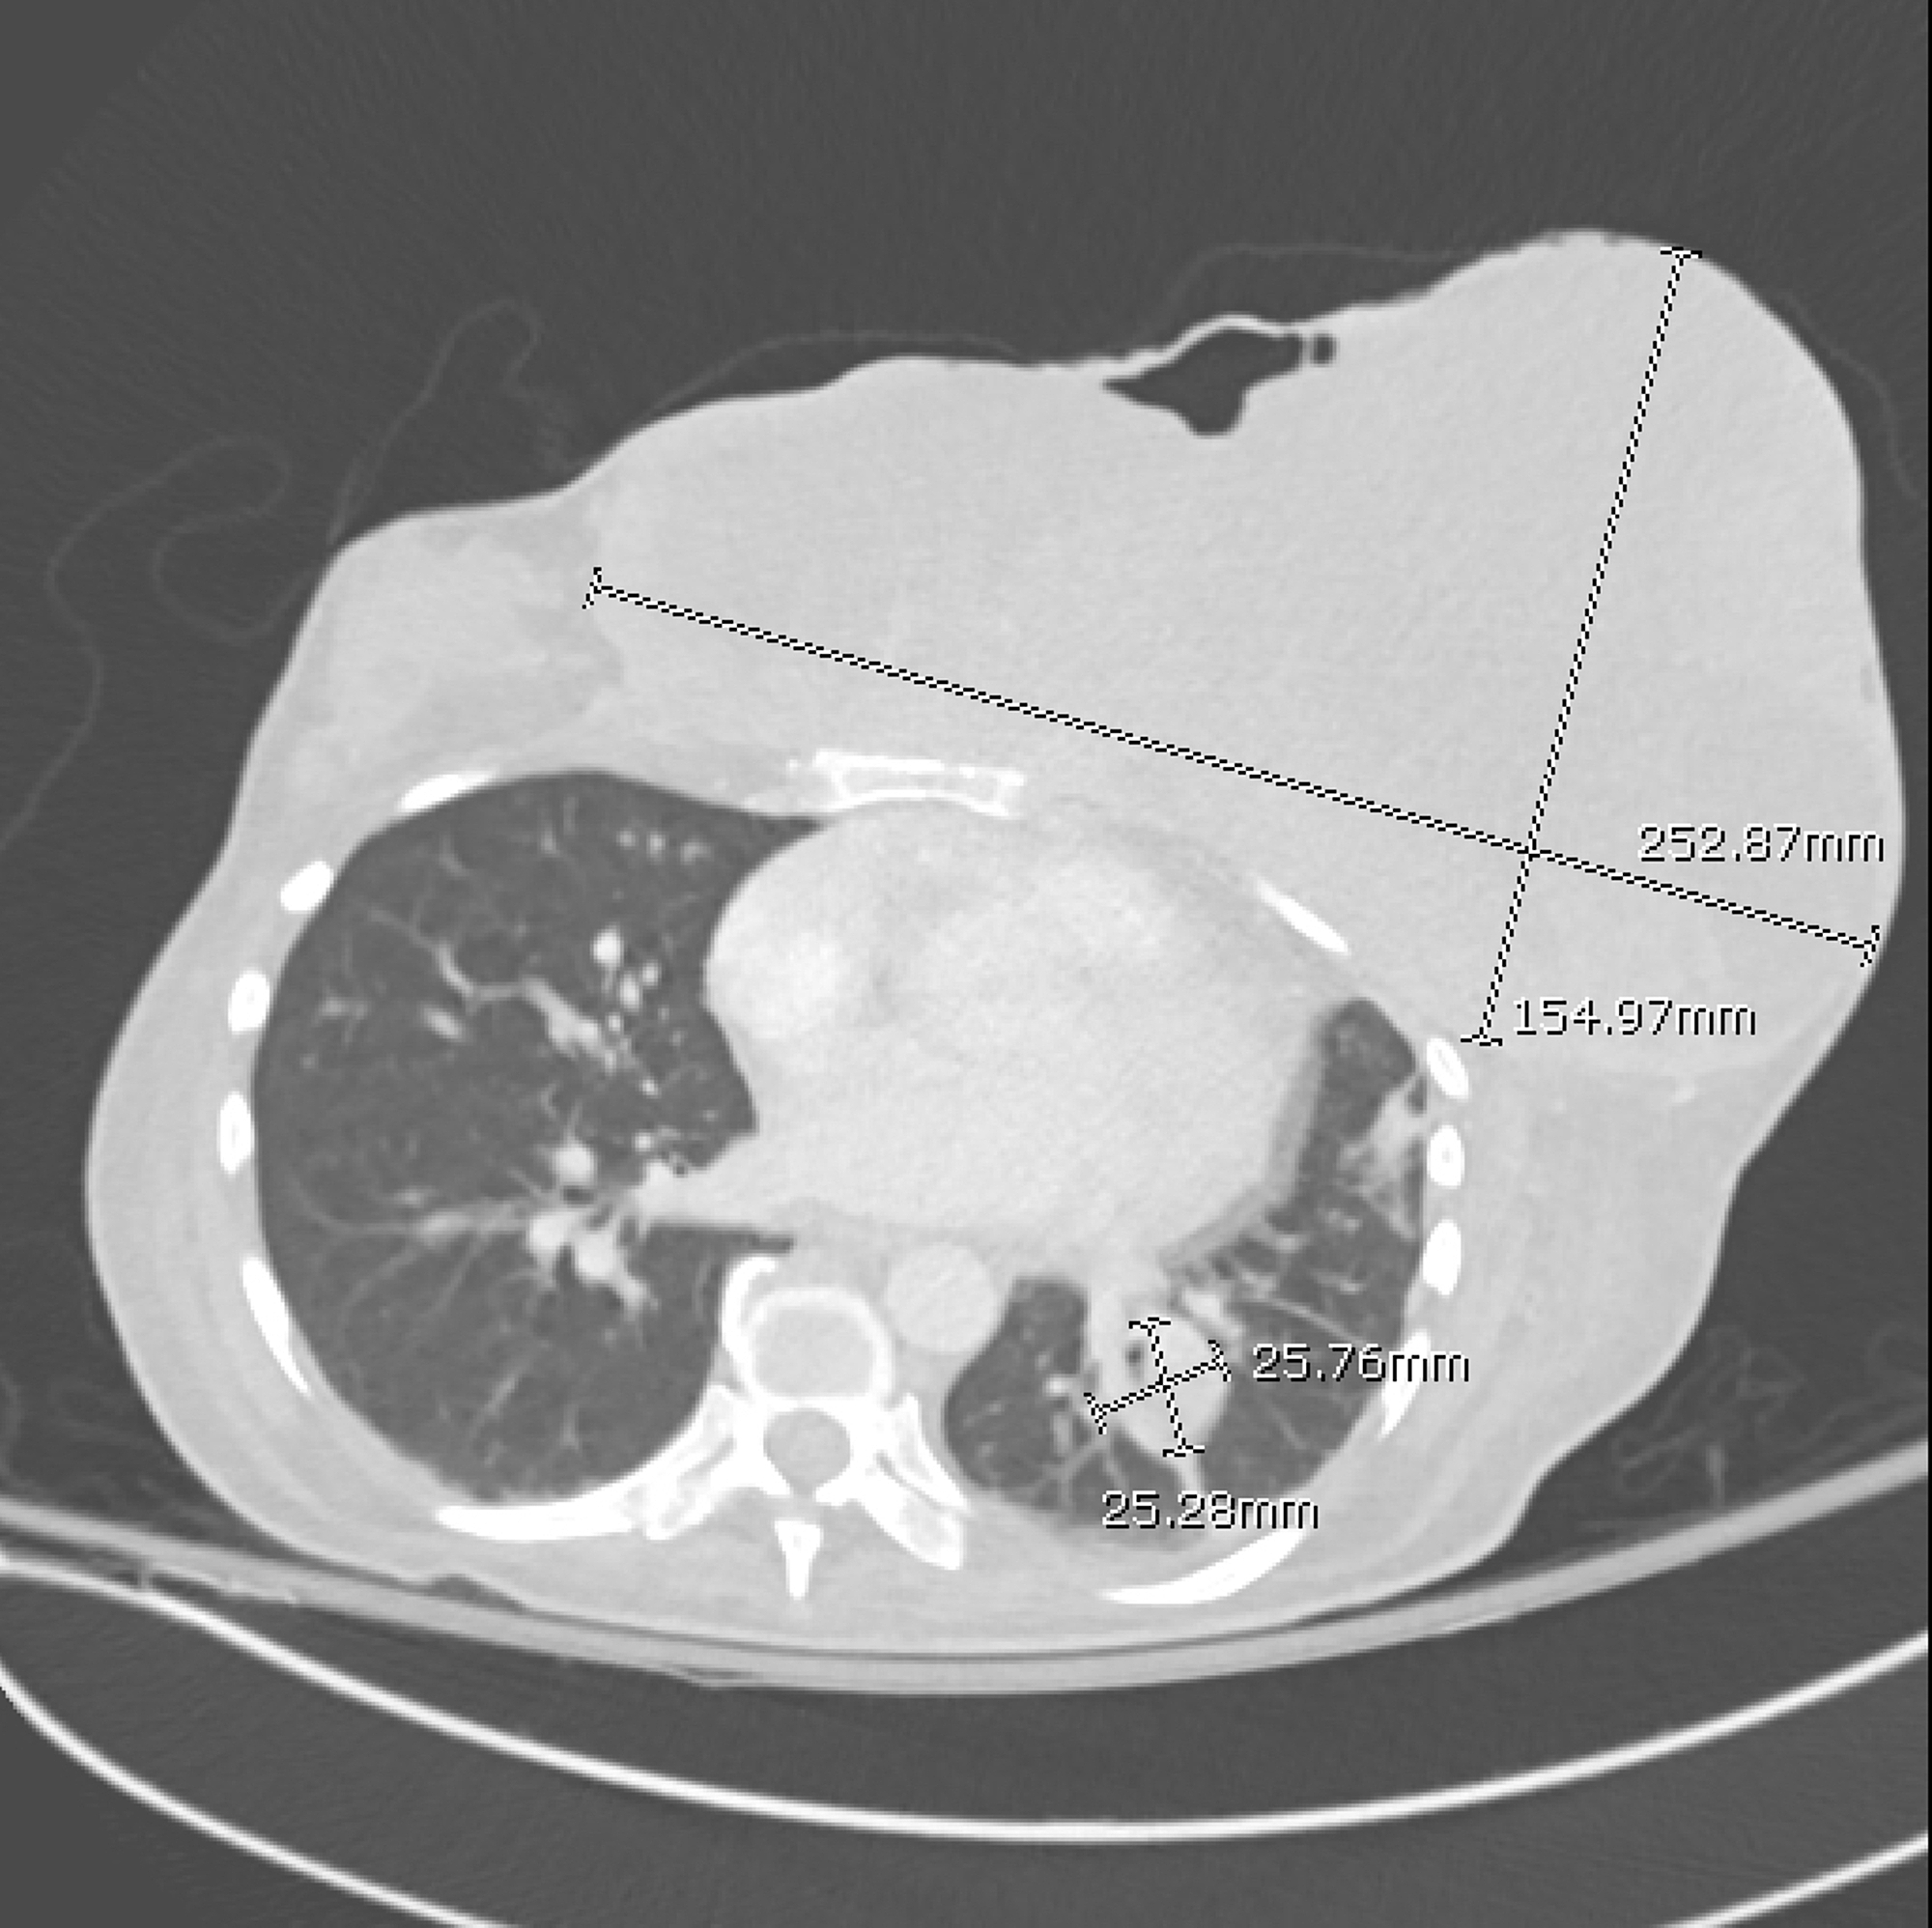

An example of spindle cell type metaplastic breast carcinoma in a Spindle Tumor Breast spindle cell carcinoma of the breast is a rare and aggressive histological type of carcinoma, which may present with benign. Spindle cell carcinoma is a rare, metaplastic breast cancer (<1% of all breast carcinomas), with reportedly triple. primary malignant spindle cell tumors are rare constituting 1.0% of breast malignancies. here we present the first known case report. Spindle Tumor Breast.

Figure 3—46 from Imaging Features of Spindle Cell Breast Lesions Spindle Tumor Breast here we present the first known case report of a patient with spindle cell carcinoma of the breast successfully. spindle cell carcinoma of the breast is a rare and aggressive histological type of carcinoma, which may present with benign. Spindle cell carcinoma is a rare, metaplastic breast cancer (<1% of all breast carcinomas), with reportedly triple. breast. Spindle Tumor Breast.

Figure 1 from A Case of Spindle Cell Carcinoma of the Breast Visualized Spindle Tumor Breast spindle cell lesions of the breast represent a broad spectrum of entities, ranging from nonneoplastic. breast spindle cell lesions are generally classified into two main categories: here we present the first known case report of a patient with spindle cell carcinoma of the breast successfully. primary malignant spindle cell tumors are rare constituting 1.0% of breast. Spindle Tumor Breast.